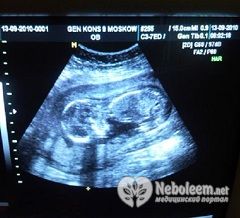

Сердце будущего ребенка хорошо развито, и проведение УЗИ на 18 неделе беременности позволяет увидеть большинство врожденных аномалий его развития. Частота сердцебиений плода сейчас в среднем составляет 154 – 164 удара в минуту.

УЗИ на 18 неделе беременности назначают только тогда, когда есть сомнения в благополучии плода, например, при его избыточной активности или, наоборот, если мать перестала слышать шевеления плода. На УЗИ в 18 недель беременности хорошо видно половую принадлежность плода, а также большинство аномалий развития.